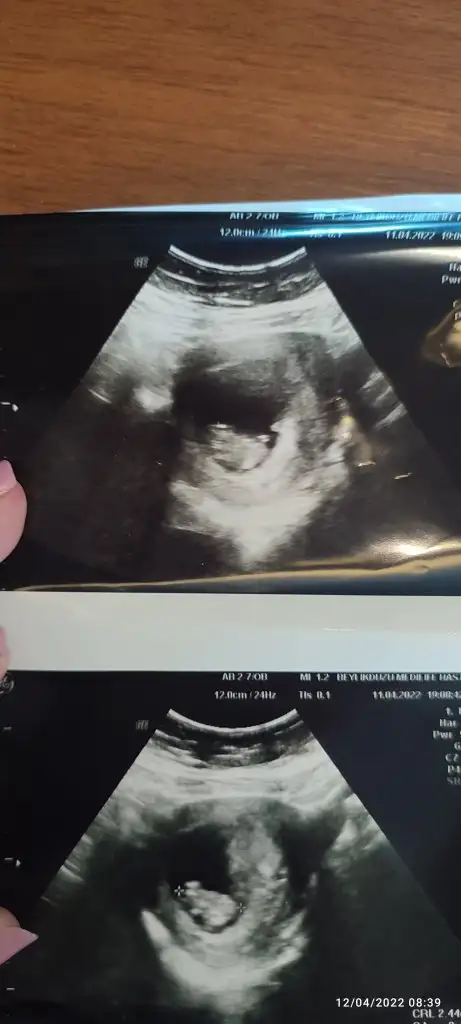

Karindan bakildi 7+1 , tahmin edebilinir mi dersiniz?:)

Slm canım nasılsın bakalım 🥰 9+1 deyiz tekrar bakıp yorumlayabilir misin rica etsem 🥰